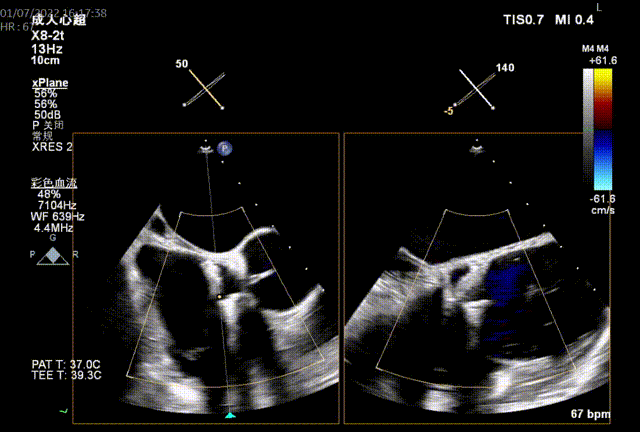

图1:术前TEE

术前TEE提示三尖瓣瓣叶活动尚可,无明显脱垂,隔瓣较短,反流束来源于前瓣及隔瓣交界处,前瓣及隔瓣对合缘保留良好,反流束同时向后隔交接延申。